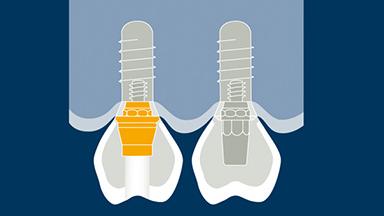

O projeto de todas as próteses sobre implante deve ser baseado em um plano protético e deve abordar todos os fatores de planejamento específicos identificados como relevantes. Há vários aspectos que são comuns ao planejamento da maioria das próteses fixas sobre implante (ou PFs), e é útil organizar esses pontos em uma sequência lógica de planejamento. O primeiro ponto é a seleção do tipo e configuração da PF. O próximo ponto é a seleção do método de retenção, seguido da consideração dos aspectos externos e da estrutura interna necessária para abordar fatores como estética, função e força. Este módulo examinará cada um desses pontos de planejamento, por sua vez. Os Módulos de Aprendizado da Academia, mais detalhados e separados, baseiam-se no presente Módulo e abordam a seleção de materiais restauradores para a PF, a seleção de pilares e a configuração dos implantes.

- selecionar o método de retenção